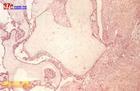

病灶内肉眼可见到葡萄状物,个别看不到葡萄状物,但镜下有绒毛结构。其浸润能力较葡萄胎为强、常侵及深部肌层,偶尔亦有穿破子宫壁造成穿孔,甚至向周围组织浸润,或向肺部、阴道等处转移。镜下所见多为增生的滋养细胞,可见到绒毛结构,这是与绒毛膜癌的区别之点,病灶周围常有明显出血。